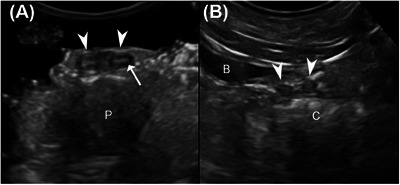

In veterinary medicine, deferent ducts are described as being visible on ultrasound only when pathologically enlarged. Abnormal ultrasonographic enlargement of the deferent ducts has primarily been described secondary to infectious and neoplastic diseases; however, no studies have evaluated the normal ultrasonographic features of these structures. This prospective observational study aimed to describe the ultrasonographic appearance of deferent ducts and assess ultrasound reliability in their identification in intact and neutered dogs without genitourinary disease. The study aimed also to compare ultrasonographic measurements with postmortem anatomical ones and to investigate the relationship between duct identification, size, and intrinsic factors of the patient. The study consisted of ex vivo and in vivo phases in which ultrasonographic assessments of the ducts were conducted at the level of the prostate in longitudinal (location 1) and transverse (location 2) planes and the inguinal canal (location 3) and scrotal region (location 4) in longitudinal planes. A total of 80 deferent ducts were included. The ducts were visible as paired tubular hypoechoic structures delimited by two thin hyperechoic lines, with a target-like appearance on the transverse plane. The deferent ducts were identified in 97.5% of our population in at least one location, with locations 1 and 2 being the most reliable ones. Identification of the ducts was independent of reproductive status; however, reproductive status appeared to be the most significant factor influencing deferent duct size, with neutered dogs exhibiting smaller deferent ducts.